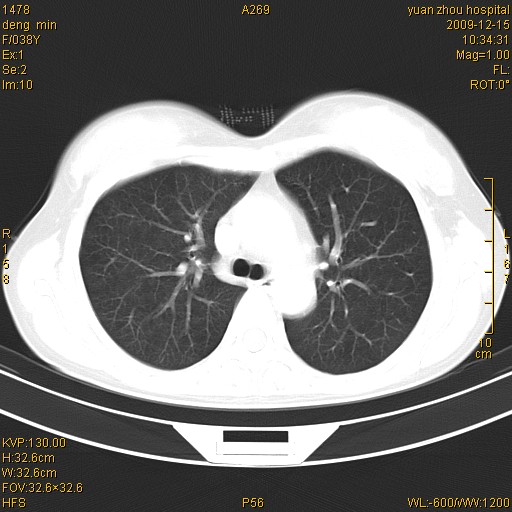

标题: CT23919:F38Y 咳嗽月余 [打印本页]

标题: CT23919:F38Y 咳嗽月余

支气管扩张。典型。

右肺中下叶、左肺上叶舌段及左肺下叶支气管扩张合并感染。